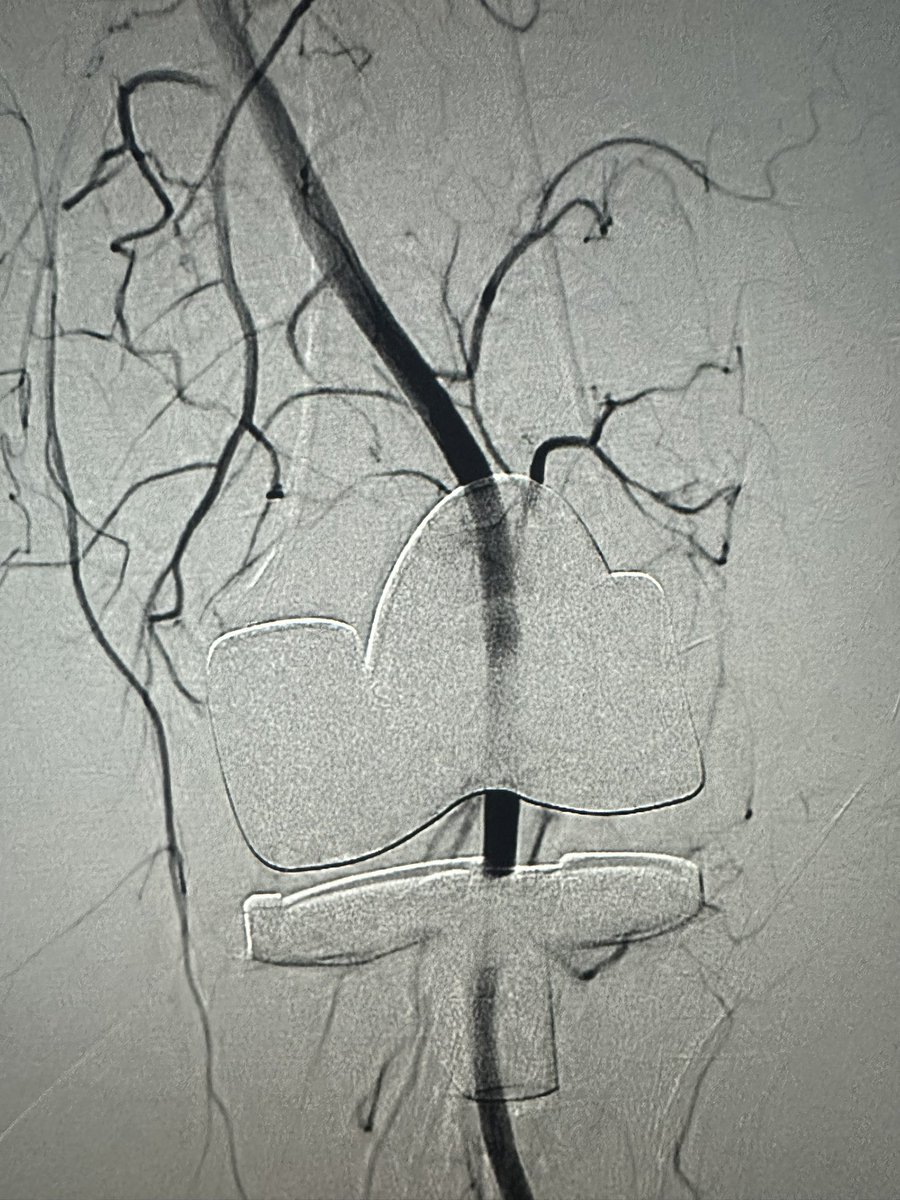

Omar Chohan, DO

Omar Chohan, DO@drochohan·

Bilateral TKR, bilateral knee pain started after left TKR. Left GAE successfully resolved pain in both knees! Patient was incredibly happy to enjoy a walk pain free. #irad #orthopedic @ChengaziMD

Omar Chohan, DO tweet mediaOmar Chohan, DO tweet media